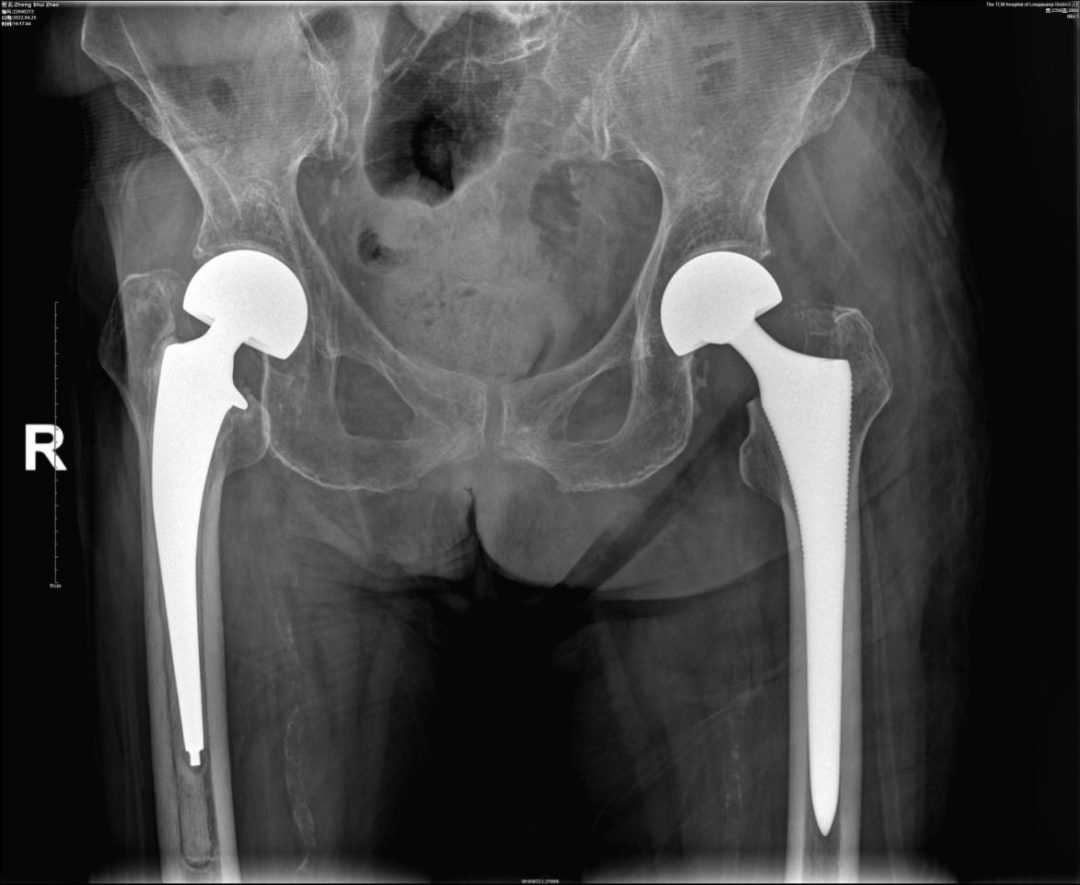

术后X片

经过充分的术前准备后,于2022年4月20日在气管插管静脉全身麻醉下,徐驰主任及其团队为钟奶奶实施了“左侧人工半髋关节置换术”,手术非常顺利,术后第3天钟奶奶就下地开始走路了!目前钟奶奶已经回到家中休养一个多月了,我们电话联系了钟奶奶的家人,得知钟奶奶目前恢复很好,钟奶奶的家人对我们医院和骨科团队表示非常感谢!后期我们也会对钟奶奶的恢复情况进行定期随访和关注。